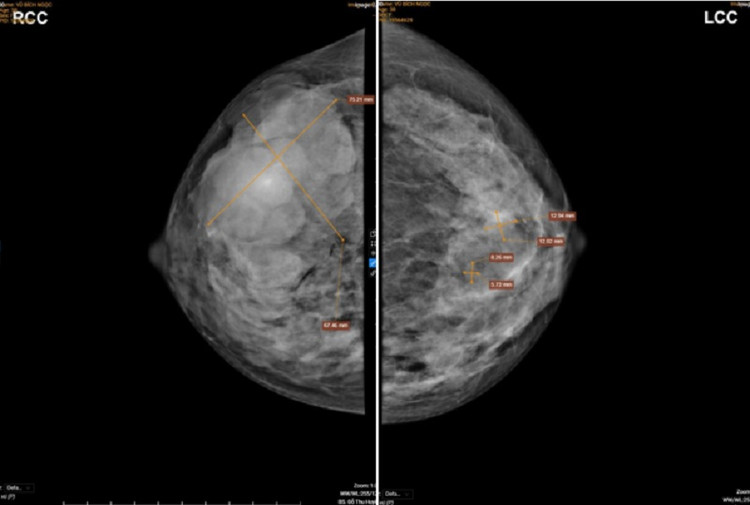

| Kết quả chụp X-quang hai bên vú của bệnh nhân cho thấy có khối u lớn ở phần vú phải. |

Để chẩn đoán chính xác bệnh, bác sĩ chỉ định bệnh nhân làm một số thăm dò, xét nghiệm cận lâm sàng. Kết quả, siêu âm tuyến vú có hình ảnh nhân tuyến vú hai bên, trong đó bên phải kích thước lớn khoảng 83x47mm; X-quang tuyến vú có hình ảnh khối tăng đậm độ nhu mô tuyến vú phải, phân loại BIRADS 4b và nốt tăng đậm độ nhu mô tuyến vú trái, phân loại BIRADS 3.